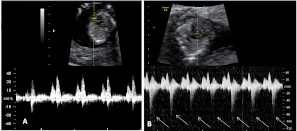

He aquí un signo inequívoco de bienestar fetal: los movimientos vigorosos de un bebé en su semana 12 de gestación. La ecografía 4D muestra al niño en movimiento, junto con la placenta y el cordón umbilical dentro de la cavidad uterina.

Ecografía en 4D de feto de 12 semanas en movimiento

La variedad de movimientos de este bebé de 12 semanas de gestación es muy amplia. Las imágenes muestran cómo cambia de postura varias veces y agita con energía brazos y piernas. Para los ginecólogos, los movimientos de la criatura indican vitalidad, son un signo positivo de salud fetal. En la ecografía en 4D (vídeo) se aprecian casi todas las estructuras externas de la criatura, además del cordón umbilical y la placenta (ambos conectados entre sí), en el margen superior izquierdo de la cavidad uterina.